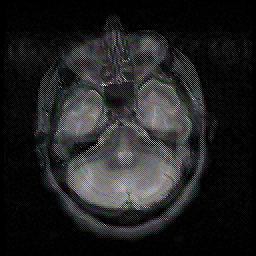

Huntington's Chorea, MR -- Slice #4

[Home][Help][Clinical] Slice 4